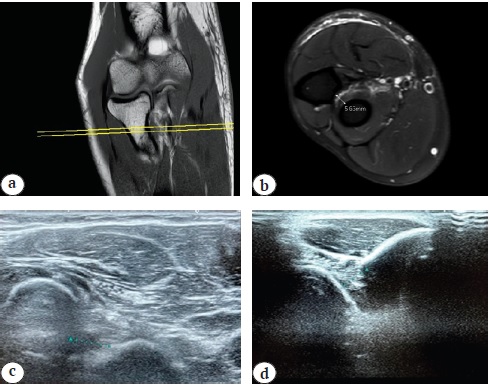

Fig. 2. Radio-ulnar space measurement example during appointment of patient with the distal biceps brachii tendon rupture: а, b — MRI (the middle third level of the “foot-print” of radial tuberosity); c, d — US (volar and dorsal accesses in pronation and supination positions of the forearm)

According to a pre-determined algorithm for choosing treatment tactics in DBT ruptures, patients underwent physical tests: O'Driscoll, Ruland, supination-pronation, comparative isokinetic (DC-100 wrist dynamometer), measurements of the biceps flexion interval were carried out, the biceps fold coefficient was calculated. In order to determine the level of tendon injury, measurement of the proximal radioulnar space (PRUS), lacertus fibrosus provocation and the degree of biceps fatty degeneration in 49 (84.5%) cases, comparative ultrasound diagnostics of elbow joints by volar/dorsal approaches was performed and in 10 cases (15.5%) — MRI of the elbow joint 1.5–3.0 Tl (2). In 2 (3.4%) cases, electroneuromyography was performed when neuropathy was suspected.